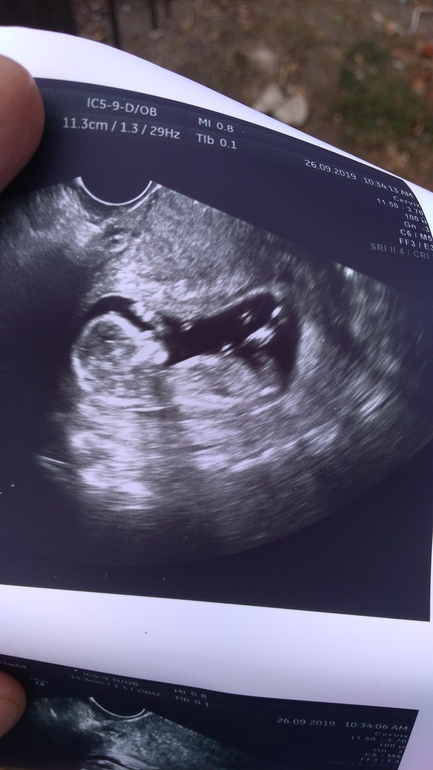

Пол малыша

Пол малышаДевочки,как вы там смотрите по бугорку?или его нет на фото?Я не понимаю ничего,но интересно,узист сказал не уверен,не стал говорить.

я бугорков вообще не вижу (да и не разбираюсь в этих углах)))) Но второе фото такое клевое!!!

Вот и у меня по задней и сказал неудачно совсем лежит,как не вертел.

Говорит бывает,что прям сразу видно,а у вас что-то среднее)))